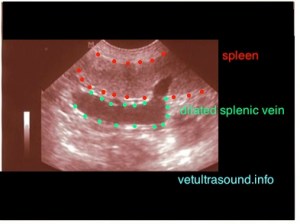

Στην παραπάνω φωτογραφία, η σπληνική φλέβα είναι διατεταμένη πέρα από το φυσιολογικό ενώ ο σπλήνας είναι φυσιολογικός σε μέγεθος. Το γεγονός οτι δεν υπάρχει ακόμα σπληνομεγαλία σημαίνει πως η ροή του αίματος στο αγγείο δεν έχει αναστραφεί.